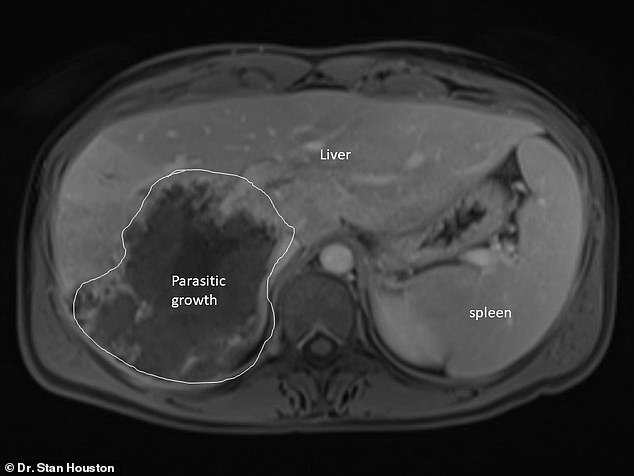

Tiến sĩ Stan Houston, giáo sư y khoa tại Đại học Alberta cho biết Armstrong là một trong số khoảng 15 bệnh nhân ở Alberta kể từ năm 2013 bị nhiễm siêu âm phế nang, một bệnh ký sinh trùng hiếm gặp do sán dây Echinococcus multilocularis gây ra. Các tế bào của sán dây sinh sôi nảy nở trong gan, gây ra sự tăng trưởng giống như khối u, sau đó có thể lan sang các cơ quan khác và nếu không được điều trị, có thể gây suy gan hoặc thậm chí tử vong, theo Hiệp hội X quang Bắc Mỹ.

Bởi vì sự tăng trưởng của kí sinh trùng lan rộng như ung thư, các bác sĩ có thể nhầm chúng với căn bệnh ung thư. Tiến sĩ Houston nói thêm: "Không ai ở bệnh viện này từng chứng kiến căn bệnh này, nên khi phát hiện một mảng tối trên ảnh siêu âm, họ đều sẽ cho rằng bệnh nhân mắc khối u."

Tiến sĩ Houston tin rằng ký sinh trùng đã phát triển trên gan của Armstrong trong khoảng từ 10 đến 15 năm. Armstrong không biết làm thế nào cô nhiễm sán dây, nhưng tin rằng cô có thể đã nhiễm ký sinh trùng trong khi sửa chữa thiết bị tại một trang trại.